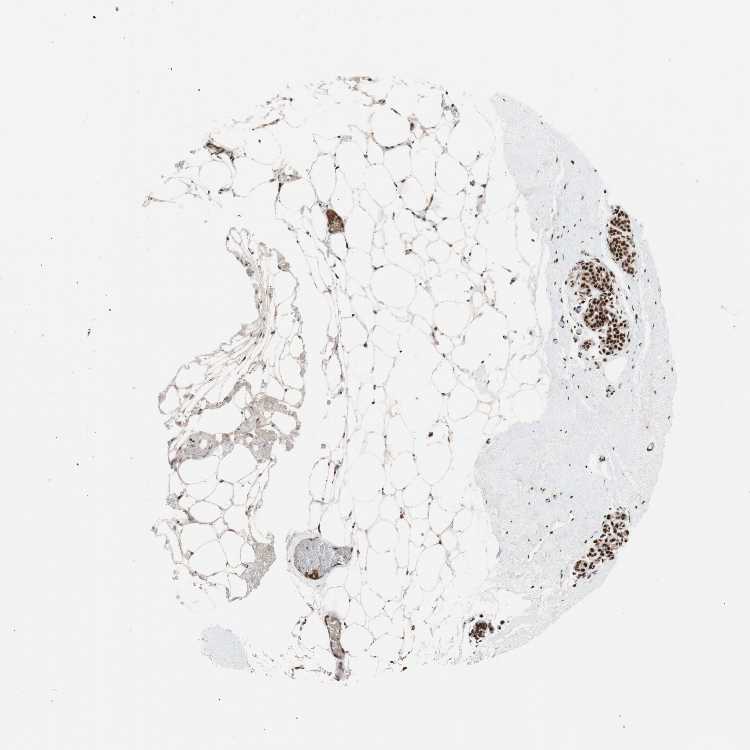

TISSUE PRIMARY DATA BREAST Show tissue menu

BREAST - Antibody stainingi

Antibody staining in the annotated cell types in the current human tissue is reported as not detected, low, medium, or high, based on conventional immunohistochemistry profiling in selected tissues. This score is based on the combination of the staining intensity and fraction of stained cells.

Each image is clickable and will lead to virtual microscopy that enables deeper exploration of all samples and also displays staining intensity scores, fraction scores and subcellular localization as well as patient and tissue information for each sample.

Antibody HPA006623Antibody HPA008900

Adipocytes MediumMedium

Glandular cells HighHigh

Myoepithelial cells HighHigh